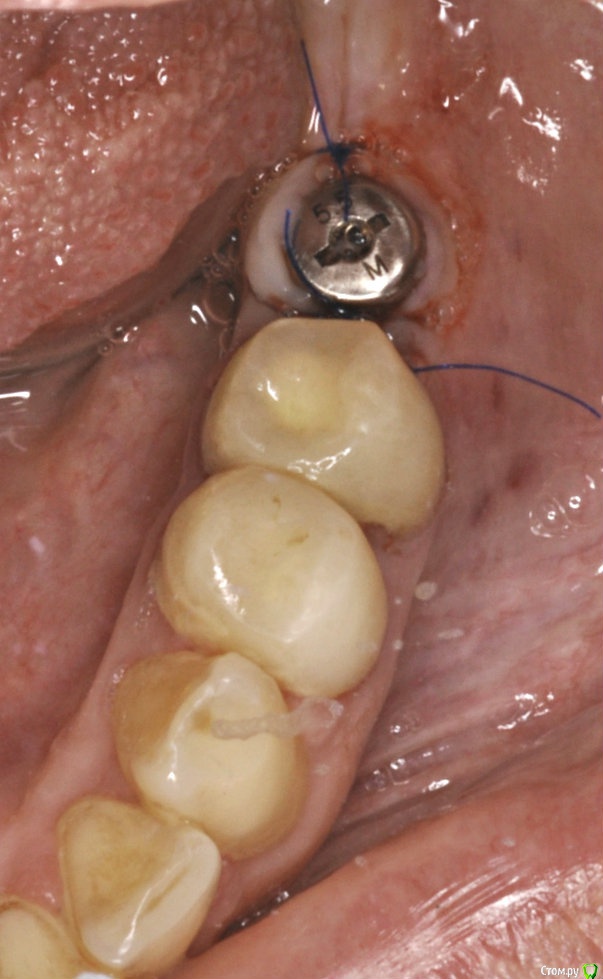

Neilrus Опубликовано 28 марта, 2017 Поделиться Опубликовано 28 марта, 2017 (изменено) Здравствуйте, коллеги. Есть пациентка, 45 лет, принимает постоянно раз в две-три недели метотриксат путем инъекции по 2,5мл по причине ревматойдного артирта.установил ей одномоментно имплантат в позицию 11 зуба с небольшой пластикой вестибулярно. торк отличный, по прошествии 3 мес через день после очередного укола метотриксата вспыл маленький свищ с белесоватым отделяемым, открыл, проверил усилие выдержал 35Нсм, установил временную коронку с подворачиваним лоскута. Все стабильно 3 недели и вот вчера очередной укол и появляется свищ уже большего размера. Возможно это от данного препарата? есть у кого-нибудь опыт с такими пациентами? ПОчитал инструкцию и обомлел (особенно про часть где совмещение с НПВС может привести к летальному исходу), ее доктор финский считает что такое возможно, но отменить или заменить его возможности нет.Она живет в финляндии раз в месяц только приезжает, рентгена нет, общаемся по вайберу, фото пока только такое, приедет ко мне 5 апреля. Изменено 28 марта, 2017 пользователем Neilrus Ссылка на комментарий

Neilrus Опубликовано 28 марта, 2017 Автор Поделиться Опубликовано 28 марта, 2017 времянка на временном титано-пластм аббатменте, не фигня какая-нибудь Ссылка на комментарий

kriokov Опубликовано 1 апреля, 2017 Поделиться Опубликовано 1 апреля, 2017 Ревматоидный и метатрексат.(тоже просил помощи у коллег) Болт в обл 36, суперлайн. фото с коронкой полгода назад ортопед сделалМне кажется свищи, это имплантат коронально "голый ", и слизистая тонкая, хотя всегда возможны другие факторы. 1 Ссылка на комментарий